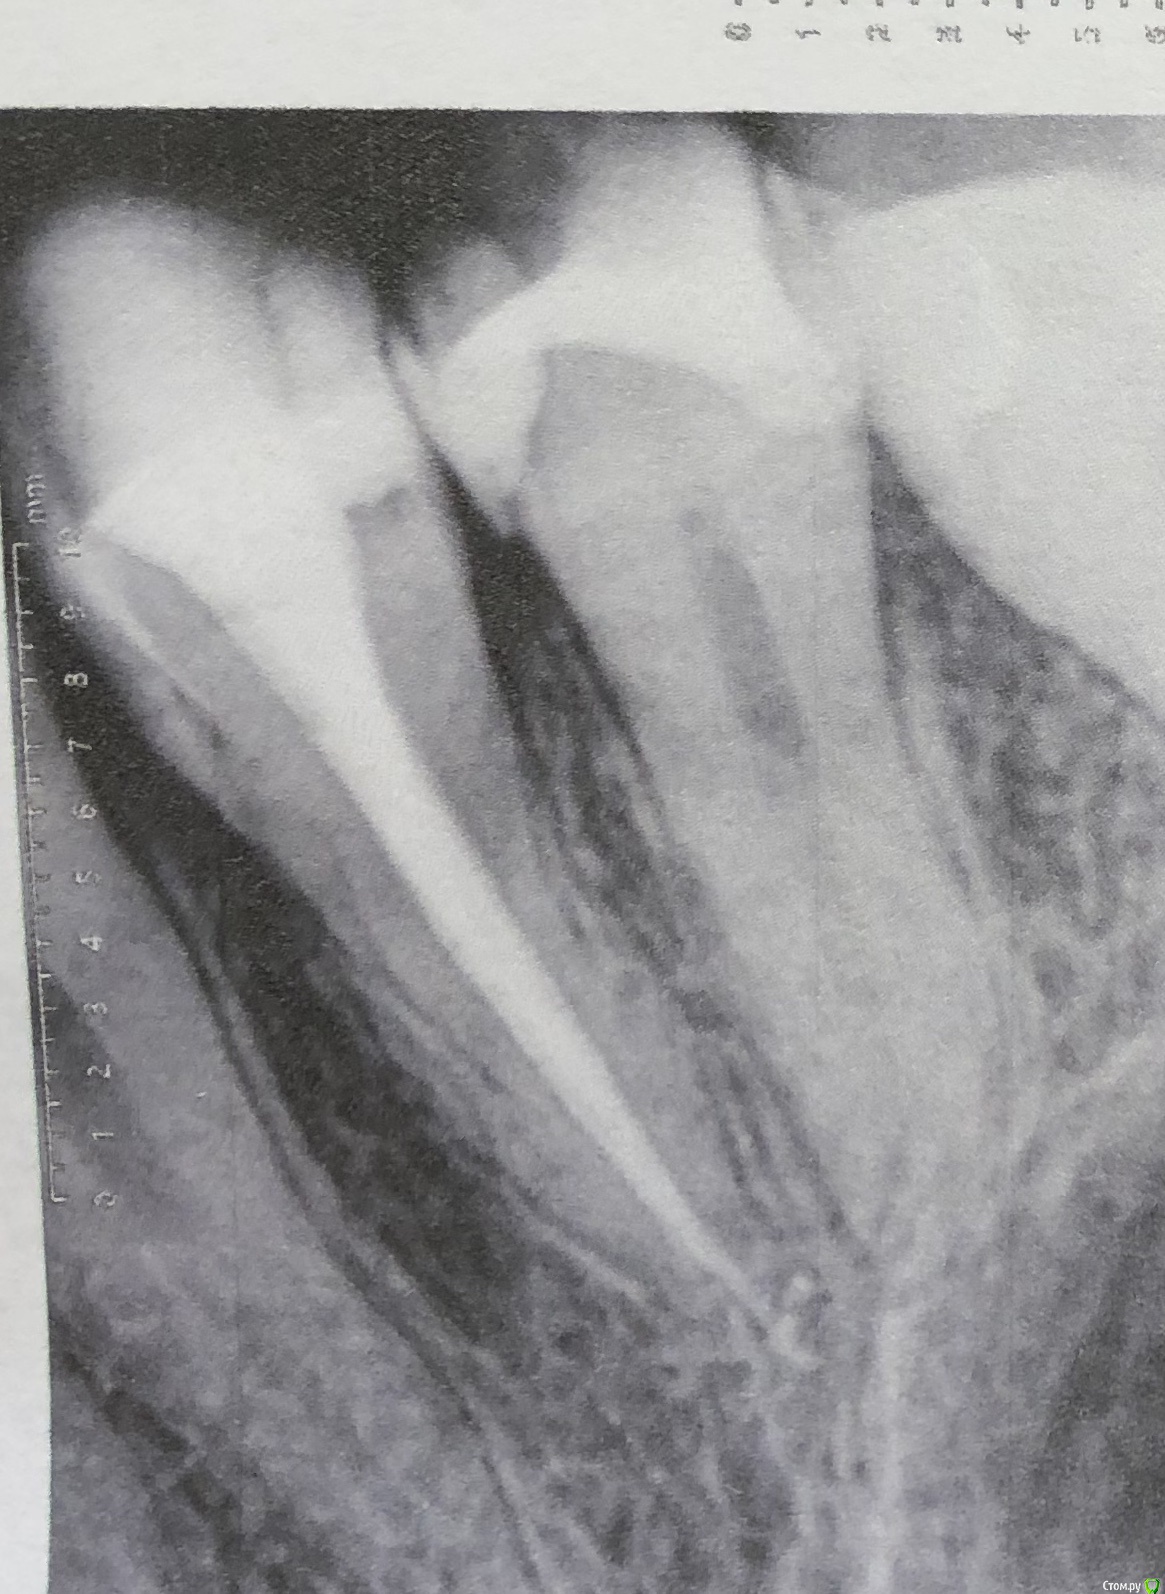

Olga2396 Опубликовано 6 октября, 2019 Поделиться Опубликовано 6 октября, 2019 (изменено) Зуб не болит 4й,но при постукивании чувствителен. Что с боку если постучат, что если постучать на жевательную поверхность.При первом лечении каналов зуб продолжал реагировать на горячее, был крайне чувствителен после горячего,языком было недотронуться. Врач перелечила каналы,боль уменьшилась,при надкусывании не больно, но непонятно почему если постучать неприятно, хотя с другими зубами у которых есть нерв нет неприятного ощущения. + переживаю из за того что выведено за верхушку корня, гуттаперча ли это? Или силлер, пломбировали мне кстати эндометазоном. Надо перелечивать? Или смотреть за состоянием зуба через пол года,будет ли увеличиваться чувствительность или уменьшаться.+ ко всему говорят об удаление нерва из 5го зуба. Зуб чувствителен на холодное,иногда горячее,но не пульсирует,ночных болей нет. Надо ли удалять? Говорят у меня анатомия зубов что нерв близко расположен к поверхности зуба,но при препарировании не была вскрыта пульповая камера и сказали дентин плотный, но 5 зуб чувствителен на холодное,но не больно,обезболивающее не пью и проходит сразу же. Я уже устала с этими зубами, вроде пролечила, а неприятных ощущения есть. 4й зуб пролечен уже как месяц. 5й пока не удаляют нерв смотря за динамикой,есть ли боли нет. Иногда сам как будто микротоком мимолетно стрельнет, ощущения как если бы укололи палец,не больно и пройдётсразу же. Не пульсирующая.1. До удаления нервов 4й5й зуб2. После удаления нерва,первая попытка (боли,чувствительностью горячее)3,4- после 2го лечения в разных боковых проэкциях снимок. Состояния на данный момент 4 и 5 зубаНа 5 снимке красным я отметила потемнее похоже на доп.ветвь канала. На снимках 3,4 есть это ответвление. Это доп. Канал?или особенность снимка? Изменено 6 октября, 2019 пользователем Olga2396 Ссылка на комментарий

red_butler Опубликовано 10 октября, 2019 Поделиться Опубликовано 10 октября, 2019 Четвертый пролечен достойно, дискомфорт при постукивании должен пройти. Зуб обязательно восстановите искусственной коронкой. Пятый, доктор оставил часть старой пломбы? По рентгену необходимости лечения каналов не увидел. По снимку есть вопросы по контактным пунктам между пятым и шестым - пломбировочный материал в межзубном промежутке, на шестом, его нужно убрать. Если боли в пятом быстро проходящие, и не исчезнут, то ставить вопрос о повторном лечении Ссылка на комментарий

Olga2396 Опубликовано 4 ноября, 2019 Автор Поделиться Опубликовано 4 ноября, 2019 Пишу почти через месяц. пломбу переделали, но блин 5й зуб реагируете на холодное все так же, при длительной нагрузке ноет. Где десна воспаляется периодически,зубная нить рвётся.Сказал врач что может отдавать так 4й, мол там корни рядом друг с другом.Сделали снимок, сказали все нормально. Но! Я боюсь меня обманывают, потому что что-то идёт не так. Если сравнить предыдущие снимки. То на 4ке у корня какое то затемнение в месте выведение материала,на предыдущих снимках такого не было. Но 4й зуб вроде не беспокоит. 5й после холода но не длительный дискомфорт, только при перкуссии и то не всегда как то, как будто если на определенный участок зуба попадёт,твёрдая пища.Что можете сказать по этому снимку? На счёт 4го и 5го.Если сравнить предыдущие. Ссылка на комментарий

Olga2396 Опубликовано 4 ноября, 2019 Автор Поделиться Опубликовано 4 ноября, 2019 (изменено) Прошу незакидывать камнями,а дочитать историю до конца и войти у мое положение.Мне зуб с гранулемой,ссылку прилагаю лечат уже почти 5 месяцев, мне кажется меня обманывают и губят мое здоровье. Кт сделано 5 месяцев назад. Сначала она врач распломбировала каналы,промывала,использовала изначально рабедарм(изоляцию),заводила лекарство. После первых манипуляций первые 5 дней, а началась я лечиться в июне, я лезла на стенку от боли,но потом боли прошли, второй раз она промыла каналы через 2 недели закладывала лекарства метапекс какой-то и каласепт,за эти 2 раза зуб вроде стих,но у меня начались проблемы с другими зубами. На снимке видно что был пульпит нижнего 6го зуба,этот зуб вроде залечили. С гранулемой забыли. чрез 2 недели его надо бы уже закрыть, но мне его раскрыли промыли(последующие разы уже не применялся рабедарм)и вроде заложили лекарство, но как оказалось нет. Тут врач неожиданно уезжает на месяц. Через недели 2 у меня зуб с гранулемой начинает снова болеть, при надкусывании, реакция на горячее, я пишу ей, она говорит дождись меня. За это время она прописала мне антибиотики амоксиклав, я пропила,стала легче. Но ненамного.Она приезжает и у меня начинаются проблемы со следующими зубами, как раз 4 и 5, там был глубокий кариес. В 4м удалили нерв, хотя он не болел, нотреагировал на холодное и сладкое,не было таких пульпитах болей, 5й долго не залечивали, так как появилась новая проблема. 6й зуб который был снизу с пульпитом, боли не проходили (первая ссылка до перелечивания) ,при постукивании болел, при нажатии болел, иногда самопроизвольно болел. Переличили, сменила пасту пломбировочную и сказала что до этого была паста ah+ И сказала запломбировала эндометазоном (после лечения) . я снова жалуюсь на зуб с гранулемой тут опять она снова берётся за 6 промывает,зуб месяц был пустым оказывается и закладывает почему то в один канал гуттаперчевый штифт с каким то лекарством и снова уезжает куда то на две недели. за эти 2 недели боли стихли но началась проблема с 4м зубом который изначально лечили также Ah + он начал дико реагировать на горячее, до зуба было не дотронуться. я ей звоню опять же она говорит ждать ее, я свято верила ей,пока мое лечение не затянулось до настоящего момента,поэтому всю историю излагаю здесь. Она приезжает перелечивает зуб 4й и боли моментально проходят, в этот же день, на что она мне говорит что запломбировала очень хорошим французским лекарством под названием эндометазон с гуттаперчевыми штифтами,что мол,он якобы с противомикробный действием и даже если там что то осталось,эндометазоном убьёт микроорганизмы. Не знаю так ли это. Проблемы с зубом с гранулемой остались все так же нерешенными по сей день, а прошло 5 месяцев. Когда я уже пришла и сказала давайте как то уже будем решать вопрос с зубами и будем иметь хоть какую то монотонную работу, она прям реально так с особой серьезностью сказала что дада щас заложим лекарство и запломбируем его скоро. Назначили встречу она промывает мне зуб за 15 минут и отпускает говорит все. Теперь через 3 недели,мол типа в отпуск ухожу на следующей неделе. Я тогда подумала ну ладно, кальций она вроде мне заложила. Как оказалось всего в 2 канала, я это увидела по снимку и спросила почему так. Она сказала в другие смысла нет закладывать и она делала так ПОСТОЯННО. Там нет воспаления. Но через 4 дня почему зуб начал реагировать снова на горячее,боль была как будто по самим границам колонковой части, а не на середине жевательной поверхности зуба.Надкусить было неприятно не сказать что больно, о своих ощущениях она говорила сообщать,ну я и сказал, а так как она собралась идти в отпуск она передаёт меня другому врачу. Все это реально затянулось на 5 месяцев. (Я могла прийти на приём к ней, а она уйти или так же снова уехать куда то на неделю на две и лечение ещё затягивалось на неделю. Я рассказала малую часть, встречи переносили и лечение затягивалось,затягивалось, пока не привело меня сюда и сомнения в её квалификации или желании вылечить мои зубы.) Следующий врач говорит что все это затянулось и говорит слишком долго зуб был открыт без пломбировки. Промывает мне его, пробивает каналы и говорит что у меня там гной типа, тянется за сухими штифтами, и что странное я не знаю кому верить, та врач которая щас в отпуске говорит что там налёт на каналах типа творога, а эта врач говорит что там не налёт а «сопли» каки то тянется из двух каналов. И что ещё более странное у врача которая в отпуске длинна каналов была 17,18. А у этой 15,14 Как может расходиться длинна каналов? Он же у меня не изменяется за весь период...кому верить? Измеряли обе аппекслокатором... последний снимок зуба с гранулемой когда последний раз промыли мне зуб, 2 дня было хорошо все. А на 3й начались такие боли, что не то что надкусить, он у меня пульсировал так что не помогали обычные таблетки типа ибупрофена, помог только кеторол.+ ещё вопрос. У меня зуб который 6 снизу был с пульпитом периодически будто бы простреливает в районе между 5,6. Говорят что такого быть не может каналы запломбированы хорошо,но что я заметила,очень спилили коронку зуба и прикус снизился. Что скажете по снимку? Снимок в настоящее время.Простите за много слов, я очень устала от болей. Просто описала всю ситуацию. Вывод и вопросы: 1.Что делать с зубом у которого гранулема? 5 месяцев лечат,то забывают про него, то снова закладывают лекарство. В данный момент мне уже врач (к которому меня передала та которая ушла втотпуск) говорит просто в следующее посещение промоем и поставим постоянную пломбу. Я напротив но боли сейчас стали ещё сильнее, как при первом визите в июне. За все время я то забыла про зуб с гранулемой то снова вспоминала,вполне болей. Посещала я врача по расписанию. И каждый раз там снова появлялся налёт как мне говорила предыдущая врач. Нормально ли лечить зуб так долго 5 месяцев? Или это повод пойти к другому? Или пойти жаловаться вообще? Какой протокол лечения таких зубов. 2. Что с 6м снизу? Может там тоже Каналы плохо пролечены? Что периодически простреливает между 5,6 как будто. Или это десна? Или это вообще из за того что прикус снизился на этой стороне? Зуб явно если посмотреть срез Кт и снимок в настоящее время ниже чем должен был быть,может нагрузка идёт не на жевательный зуб поэтому так стреляет?3. Что с 4м депульпированный зубом сверху? там нет никаких воспалений на верхушке корня? И по 5 рядом что скажите какие прогнозы на данный момент? разница снимков в месяц Изменено 4 ноября, 2019 пользователем Olga2396 Ссылка на комментарий